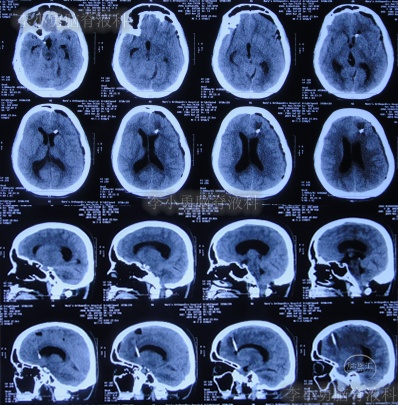

患者2019年2月初,因数次出现发作性黑蒙,2019年2月10日就诊于当地的河南省永城市某医院,查头颅CT未见明显异常(图-1);次日再查头颅核磁、颈椎核磁(图-2、图-3)后发现小脑扁桃体下疝畸形合并脊髓空洞。

图-1:2019年2月10日头颅CT

图-2:2019年2月12日头颅核磁

图-3:2019年2月13日头颅核磁